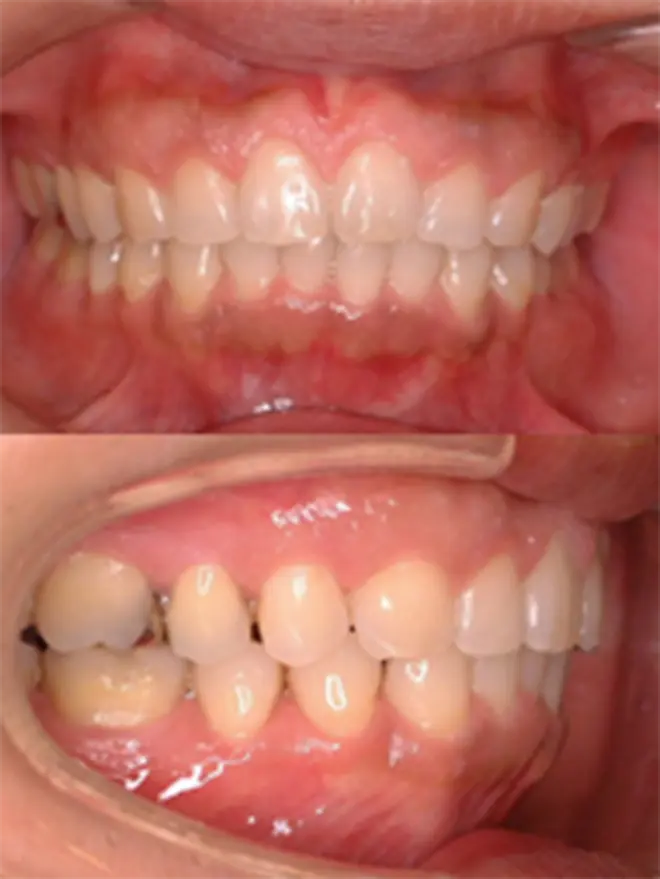

| 患者さまの年齢・性別 | 20代・男性 |

|---|---|

| 治療期間 | 2年 |

| 治療費(税込) | 1,056,000円 |

| 主訴 | 前歯で噛めない。 |

| 診断名・主な症状 | 開咬をともなう下顎前突 |

| 治療に用いた主な装置 | セルフライゲーションブラケット装置(デイモンシステム)、歯科矯正用アンカースクリュー |

| 治療内容 | 下顎の左右奥に1本ずつ歯科矯正用アンカースクリューを埋入し、その力で下顎歯列の後方移動と前歯の噛み合わせの調整を行ないました。 |

| 抜歯部位 | 非抜歯 |